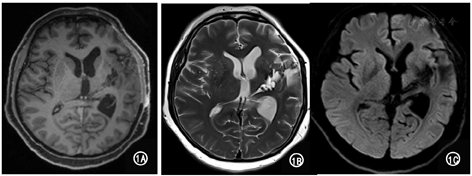

入院后专科查体:左侧肢体肌力、肌张力正常,右侧近端肌力3级、远端肢体肌力0级,肌张力明显增加,感觉未见明显异常。右上肢运动功能:Fugl-Meyer运动功能评分2分(总分66分);华山分级:Ⅰ级;改良Ashworth分级:3级。头颅核磁平扫示:左侧基底节区、丘脑软化灶,左侧额颞叶萎缩,侧脑室增宽,如图1所示。